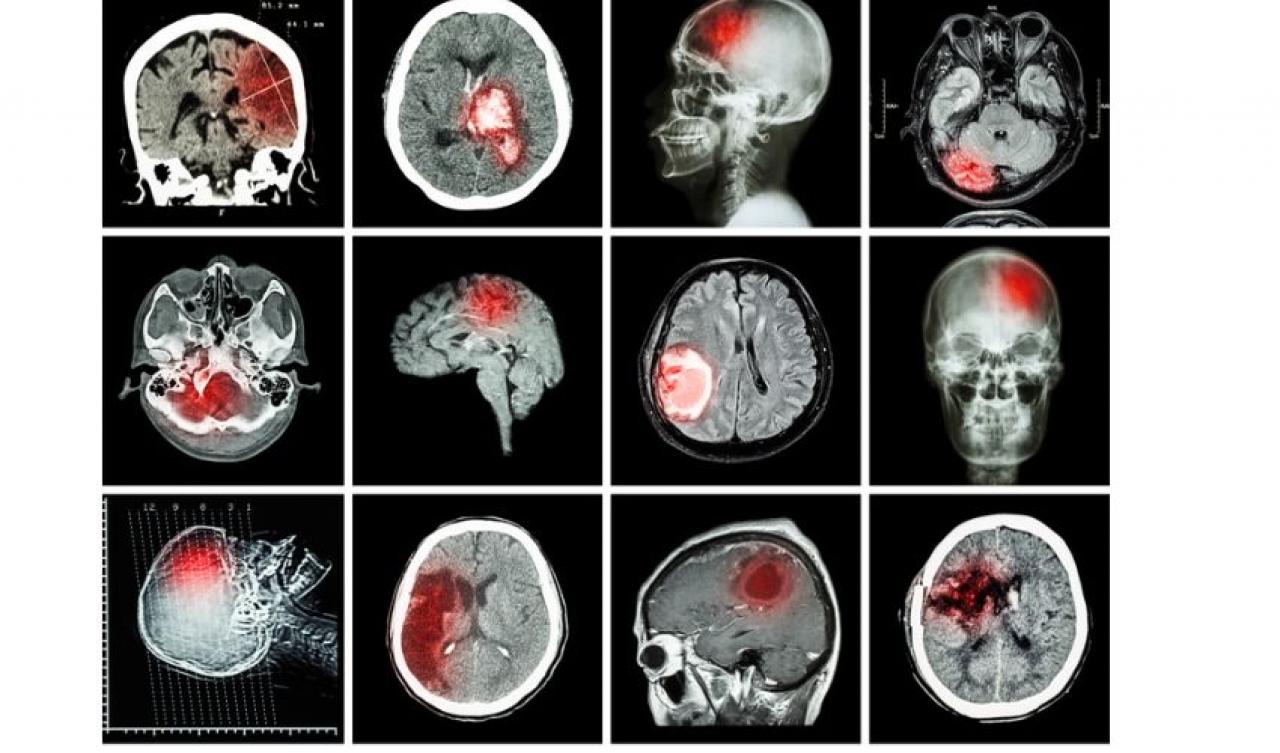

İnme, beyin damarlarında meydana gelen tıkanıklık veya kanama nedeniyle beyin hücrelerinin hasar görmesiyle oluşan bir hastalıktır. Beyin hücreleri oksijen ve besin maddeleri alamadığında zarar görür ve bu da belirtilere yol açar. İnme, beyne giden kan akışının kesilmesi sonucu meydana gelen iskemik inme veya beyin damarlarında meydana gelen kanama sonucu meydana gelen hemorajik inme şeklinde ortaya çıkabilir. İnme, özellikle yüksek tansiyon, sigara kullanımı, kalp hastalığı, yüksek kolesterol, diyabet gibi risk faktörleri olan kişilerde daha sık görülür. İnme, hızlı müdahale edilmediği takdirde ölümcül olabilir ve uzun süreli sakatlıklara yol açabilir. Bu nedenle, inme belirtileri fark edildiğinde acil tıbbi yardım alınması şart koşuluyor.

İnme tedavisi, hastalığın tipine ve şiddetine bağlı olarak değişebiliyor. İskemik inme tedavisi genellikle kan pıhtılarını eritmeye yardımcı olan ilaçların kullanımını içerir. Bu ilaçlar, pıhtının erimesine yardımcı olarak kan akışının düzeltilmesine yardımcı olur. Bazı hastalarda, kan pıhtısını doğrudan çıkarmak için cerrahi müdahale gerekebiliyor.

Hemorajik inme tedavisi, kanama kaynağının kontrol edilmesini ve kanama bölgesinin küçültülmesini içerebilir. Cerrahi müdahale, kanama bölgesini boşaltmak veya kanama kaynağını kapatmak için yapılıyor.